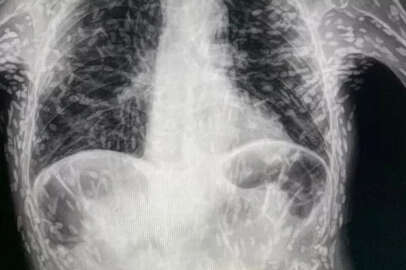

Brezilyalı doktorlar, kendilerini şaşırtan bir vakanın röntgen görüntülerini paylaştı. İyileşmeyen öksürük ve baş ağrısı şikayeti olan hastanın uzun bir zamandır tenyalar tarafından tarafından organlarının delik deşik edildiği ortaya çıktı. Bilim insanları, parazit hastalıkların ölümcül olabileceğini belirterek, gıda hijyenine dikkat edilmesini istedi. Brezilyalı doktorlar, kendilerine öksürük ve baş ağrısı şikayetiyle gelen bir hastanın vücudunun yüzlerce tenyaya ev sahipleri yaptığını ortaya çıkardı.  Bir doktorun Twitter'da paylaştığı  röntgen, her biri bir parazitin yerleşmiş  kalıntılarını temsil eden yüzlerce parlak lekeyi gösterdi. Sistiserkoz olarak adlandırılan durum, normalde bağırsaklarda yaşayan bir tenya türünün larvalarının kas veya beyin gibi dokulara girmesiyle ortaya çıkıyor. İnsanlar, başta et ve yıkanmamış meyve ve sevze olmak üzere kontamine yiyecekleri kazara yutarak bu tenyalar ile enfekte oluyor. Larvalar, deriden hissedilebilen kistler şeklinde  sert yumrular oluşturuyor. Bununla birlikte, tenyalar hızla öldüğü için durum genellikle zararsız olarak kabul ediliyor. Ancak ölü tenyalar geride bıraktığı kistler ölüme varabilen sağlık sorunlarına neden olabiliyor. Kistler akciğerlerinize yapıştığında ise öksürük ve göğüs ağrısı oluşuyor. Diğer taraftan, beyinde veya omurilikte gelişen kistler  nörosistiseroz adı verilen bir duruma yol açabiliyor. Nörosistiseroz, tenya enfeksiyonunun en ciddi şeklini oluşturuyor ve dünya genelinde epilepsi ve nöbetlerin yaygın bir nedeni olarak kabul ediliyor. Görüntüyü paylaşan Brezilya'daki Botucatu'daki Hospital das Clínicas'tan Dr. Vitor Borin de Souza, hastanın öksürük şikayetiyle geldiğini  ve durumun MRI ile rontgen taramalarında anlaşıldığını söyledi.  De Souza, "Bu vakalarda kistleri çıkarmak için genellikle ameliyat gerekir. Kistler, tenya yumurtaları ile ilk enfeksiyondan sadece aylar veya yıllar sonra gelişebilir." dedi. Hindistan'da can almıştı Öte yandan, geçen ay, Hindistan'da bir genç tenyaların beynine yumurta bırakması ve bu durumun onu bilinçsiz bırakması nedeniyle hayatını kaybetmişti. Hindistan, Faridabad'daki ESIC Tıp Fakültesi ve Hastanesi'ndeki doktorlar, 18 yaşındaki gencin  beyninin dış tabakasına gömülü parazit kistleri buldu. Bu durumda doktorlar, tenya kistlerinin sayısı nedeniyle tipik olarak kullanılan anti-paraziter ilaçların bir seçenek olmadığını söyledi. Ciddi vakalarda, ilaçlar beyindeki iltihaplanmayı daha da kötüleştirerek durumu daha ölümcül hale getirebiliyor.